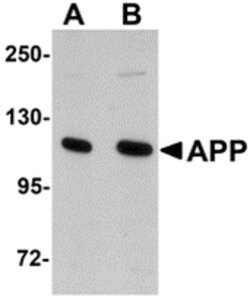

Invitrogen™ Amyloid Precursor Protein Polyclonal Antibody

Brand: Invitrogen™ PA520737

A suggested positive control is rat brain tissue lysate. PA5-20737 can be used with blocking peptide PEP-0851.

Amyloid Precursor Protein (APP) or Amyloid beta precursor protein functions as a cell surface kinesin I membrane receptor, mediating the axonal transport of beta-secretase and presenilin 1. APP is important for neurite growth, neuronal adhesion and axonogenesis. APP is a 100-140 kDa transmembrane glycoprotein that exists as several isoforms resulting from alternative splicing. Proteolytic cleavage of APP by beta- and gamma-secretases results in the generation of beta amyloid, which is the primary component of senile plaques. Senile plaques are one of the major histopathologic features of Alzheimer's disease. Abnormal regulation and processing of APP also plays a role in Down's syndrome, early onset familial Alzheimer's disease, and cerebral hemorrhage.

| Immunohistochemistry, Western Blot | |

| The immunogen is a 18 amino acid synthetic peptide within amino acids 180 - 230 of human Amyloid Precursor Protein (APP). | |

| Human, Mouse, Rat | |